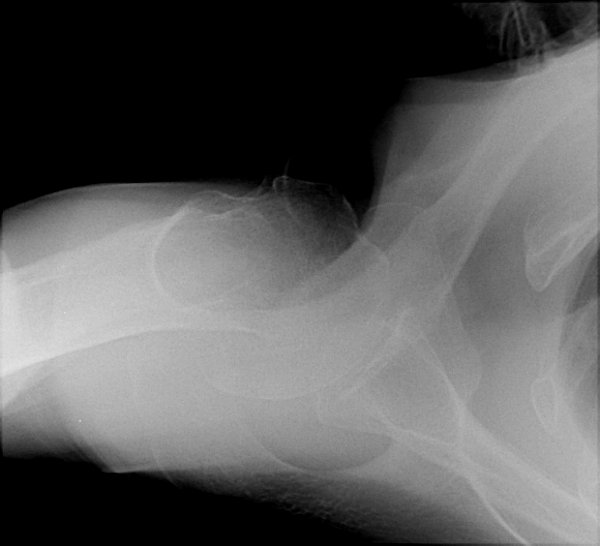

Return to Proximal Humerus Fracture